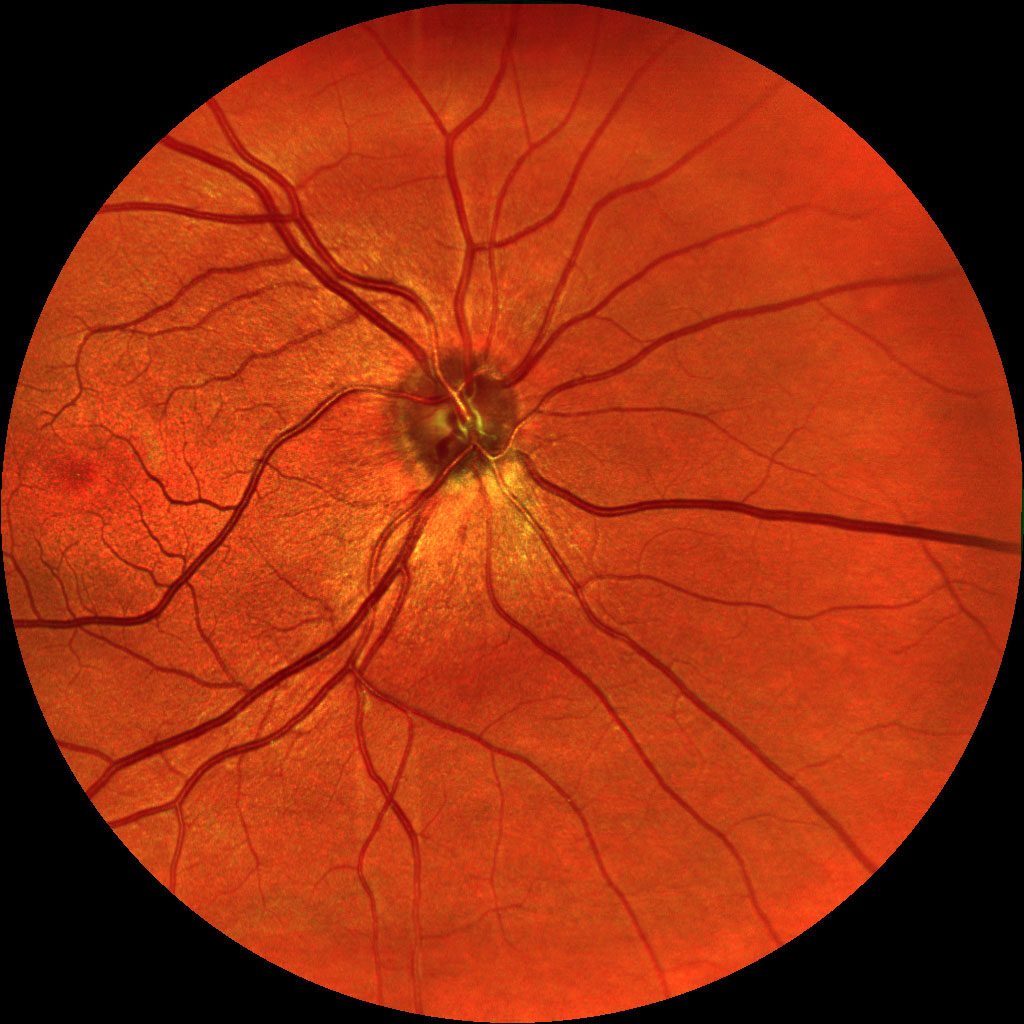

Dzięki technologi SLO – Scanning Laser Ophthalmoscope, podczerwieni oraz wiązki zielonego laseru, jesteśmy wstanie wykonać bardzo dokładny zrzut dna oka, dzięki czemu wykryjemy praktycznie każde zmiany w gałce ocznej. W realizacji takiego skanu nie potrzebne jest zakroplenie oka co znacznie usprawnia nam diagnostykę pod katem szybkości badania czy samopoczucia osoby poddanej tejże czynności. Badanie ma na celu wykrycie zmian w oku jak: jaskra, zaćma, zatory żylne, męty, retinopatie cukrzycową czy AMD(zwyrodnienie plamki żółtej), Pełna wizyta obejmuje: